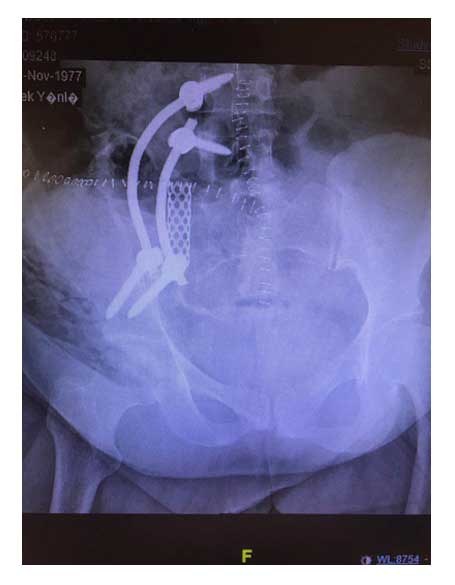

Ameliyat Sonrası: Tümör çıkarıldıktan sonra cage ve lumbopelvik fiksasyon ile yeniden yapılandırma görülmekte.

Ameliyat sonrası: Lumbopelvik fikasyon radyolojik görüntüsü